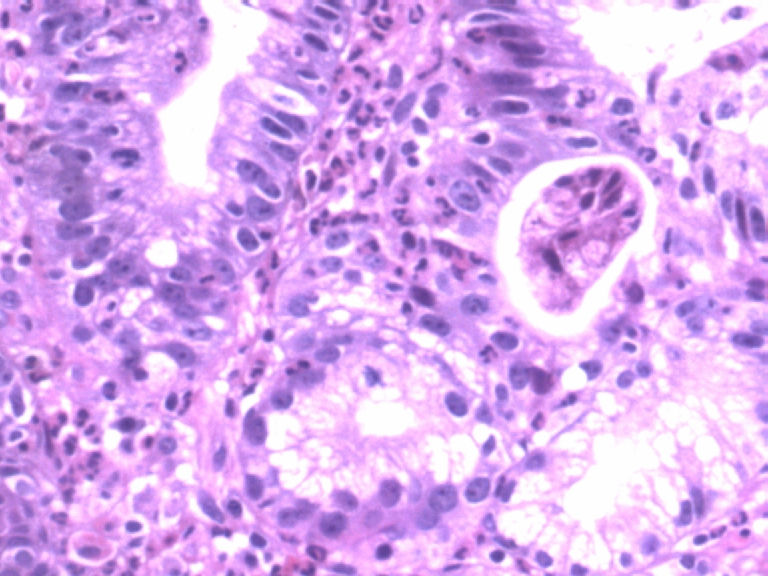

男,50岁,胃镜活检食管下段溃疡组织3块。

• 胃镜活检食管下段溃疡组织3块图2

图2

2图、3、4图上似乎有核分裂.可视为不典型增生。

请教一下2图、3、4图上似乎有核分裂如何看待? 学习了!谢谢各位老师!

核分裂在胃肠道活检中经常可以见到,结合组织形态学 细胞异型性看